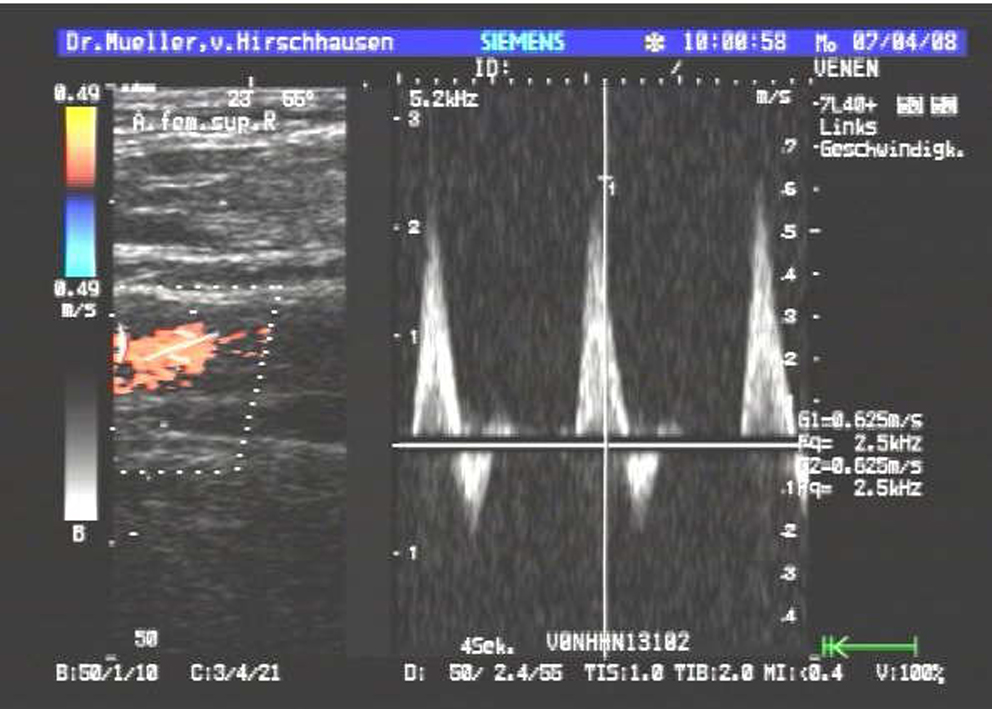

| Beinvenen und Beinarterien |

Dazu kommen neben dem üblichen schwarz-weiß Bild auch moderne Verfahren zum Einsatz wie Farbdopplersonographie und Kontrastmittelsonographie der Leber.